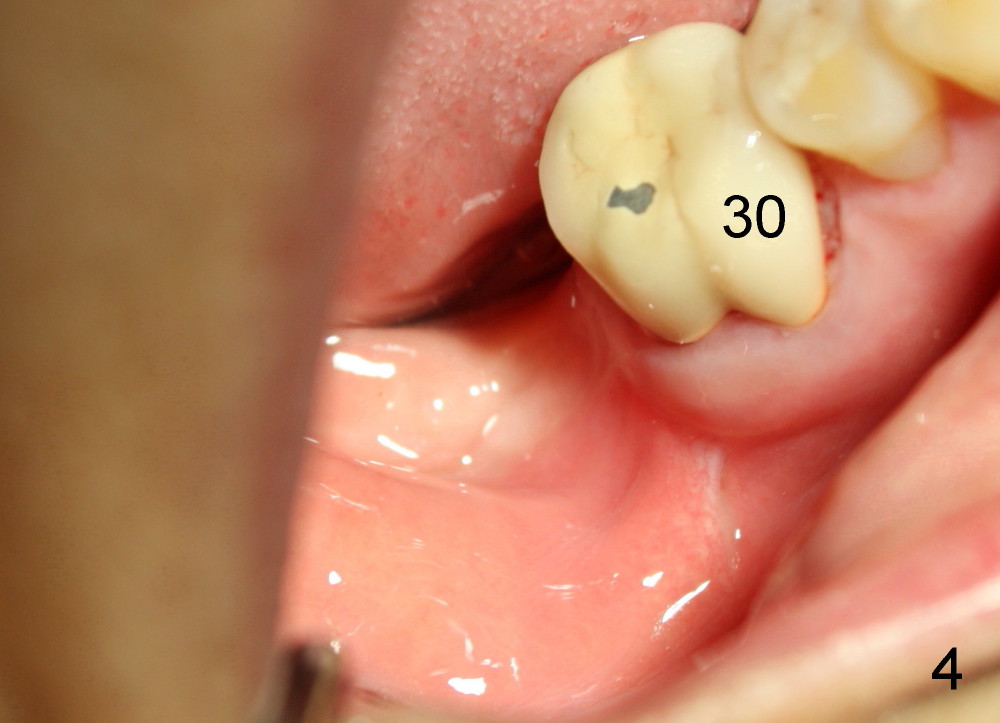

Mrs. Hwang in her sixties has had periodontal disease in her lower right 2nd molar (Fig.1 *). Three years later, both the 2nd and 3rd molars are extracted (Fig.2; pink: the upper border of the inferior alveolar canal). Four months after extraction, the patient returns for implant placement at the site of #31 (Fig.3, 4). The socket of the 2nd molar is outlined in yellow in Fig.3.

Today the patient returns for implant restoration 4 months after placement. The tissue around the implant is healthy. It appears that there is plenty of clearance (Fig.7). How much I wish no gross reduction!